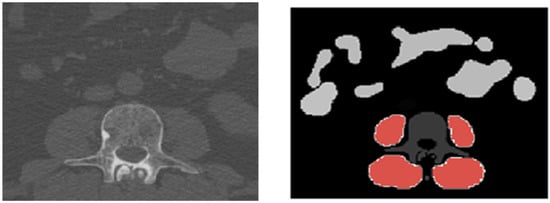

Volumetric delineation and quantification of muscle tissue rely on slice-by-slice semantic segmentation of muscle compartments. To achieve comprehensive segmentation, the open-source body and organ analysis (BOA) platform was employed [20]. BOA combines two algorithms: TotalSegmentator [21] and body composition analysis (BCA) [22]. BCA underwent training utilizing the nnU-Net framework, chosen for its robustness in accommodating diverse image dimensions and delivering adequate automated segmentation performance [19]. A manual validation process was conducted to verify the accuracy of all predicted segmentation masks in conjunction with the imaging data, ensuring the exclusion of grossly inaccurate segmentation predictions from feature extraction and preventing the use of corrupted raw imaging data (Figure 1).

Figure 1. Example of muscle segmentation. (left) Axial view of whole-body low-dose CT without contrast agent at the level of the first lumbar vertebra. (right) AI-based segmentation of autochthone muscle and psoas muscle (red) with a total volume of 1149 cm3: vertebra in dark grey and bowels in light grey.